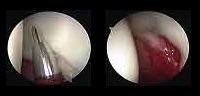

The hip joint is formed by the acetabular cavity and the head of the femur. The entire surface of the hip is covered with a smooth structure called articular cartilage which allows a smooth gliding between bones.

The practice of certain sports, especially soccer, tennis and martial arts, may cause the most common injuries such as sprains, injuries to the labrum and cartilage injuries.

Arthroscopy provides a good way to address problems within the hip joint with less tissue damage and faster recovery and comfort.